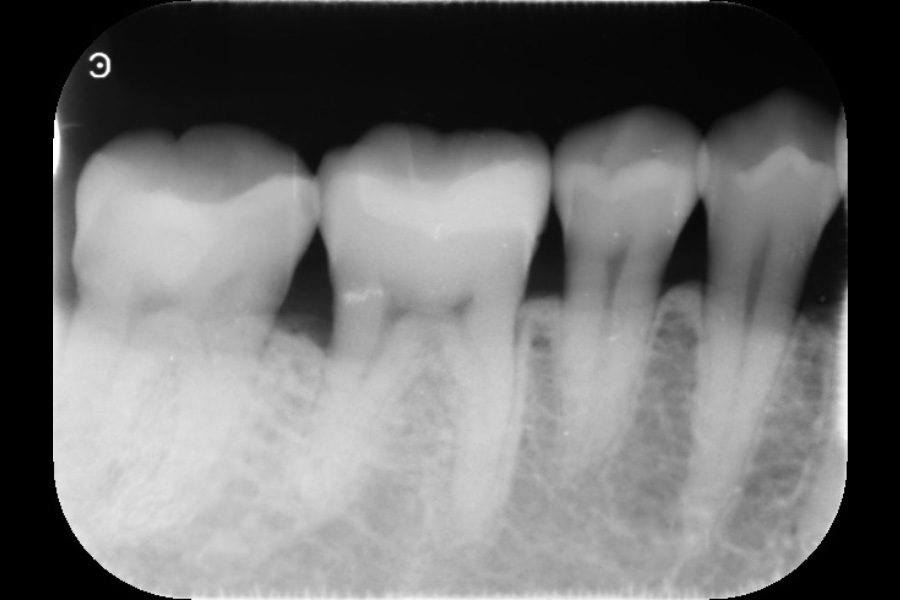

右下奥歯の歯ぐきから出血する

【歯周組織再生療法】

- 主訴

- 右下奥歯の歯ぐきから出血する

- 治療内容

- 右下4遠心に垂直性骨吸収が認められたためエムドゲインと骨補填材を用いて歯周組織再生療法を行った